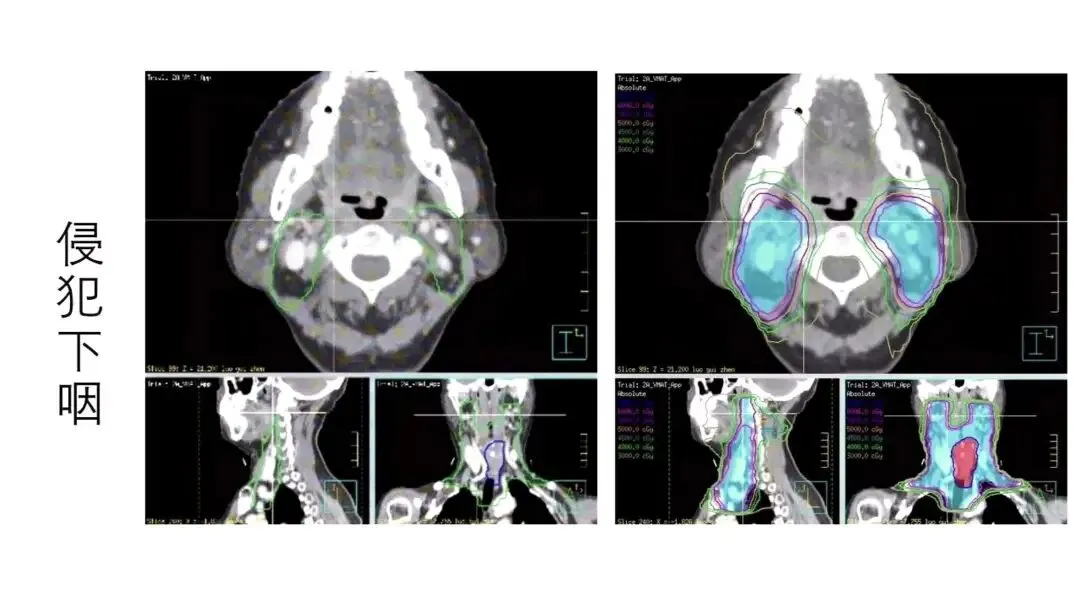

若肿瘤侵犯下咽,则咽后淋巴结转移风险显著增加(下咽后壁癌可达43.5%)。

结论:对于下咽受侵、晚期或淋巴结分期高的患者,需将咽后淋巴结纳入治疗靶区或清扫范围。